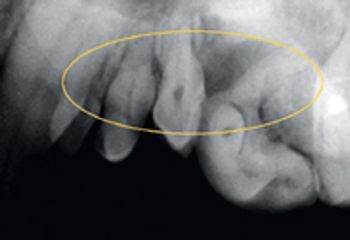

Visual examination, anesthetized probing and intraoral radiography can help veterinarians assess each patient's level of disease.

Visual examination, anesthetized probing and intraoral radiography can help you assess each patient’s level of disease.

The degree of severity of periodontal disease relates to a single tooth; a patient may have teeth that have different stages of periodontal disease. Here is an outline of the American Veterinary Dental College-approved periodontal disease classifications.